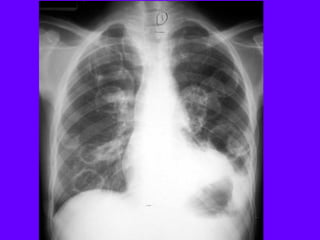

Pneumoperitoneum

Air under diaphragm

Elevated Diaphragm"

Note pneumoperitoneum

Supradiaphragmatic mass

Can be mistaken for elevated diaphragm